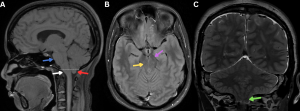

Fig 5: Figure A: Sagittal T1-weighted MRI demonstrates an enlarged pituitary gland (red arrow). Sagging of the brain is also evident, with inferior displacement of the brainstem and cerebellar tonsils (white arrow).

Figure B: Coronal T2-weighted MRI shows an enlarged pituitary gland (red arrow) extending into the suprasellar cistern and indenting the optic chiasm (green arrow).

Figures C and D. Axial and coronal T2-weighted MR images demonstrating collapsed bilateral optic nerve subarachnoid spaces (yellow arrows) secondary to low CSF pressure